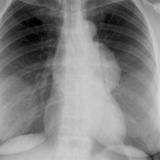

Case 9 Thymoma PA

Date: 04/04/2010

Views: 3178